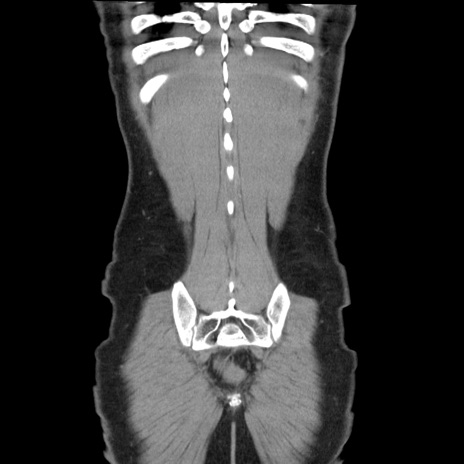

症例36(冠状断像)

【症例】20歳代 男性

【主訴】心窩部痛

【現病歴】今朝より上腹部痛あり。一旦軽快していたが再度出現したため救急要請。昨日夕に白身の魚を含む刺身を食べた。

【身体所見】BP 136/89mmHg、HR 74/min、BT 37.0℃、腹部:膨満、軟、心窩部に圧痛あり。反跳痛なし、筋性防御なし、腸雑音やや亢進あり。

【データ】WBC 17700、CRP 0.48